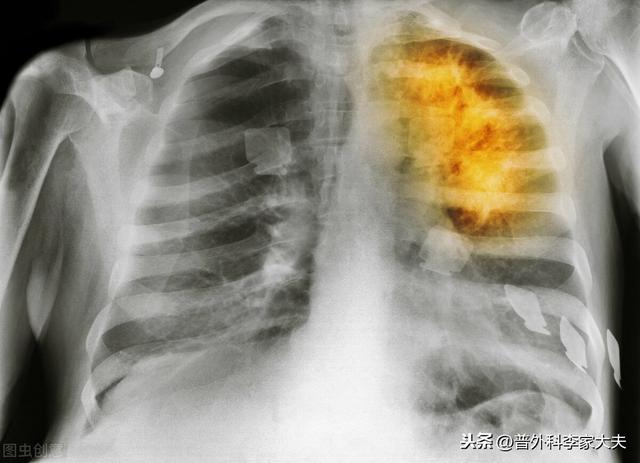

毎年80万人近くの肺がんの新規患者が発生しており、患者の約85%は非小細胞肺がんで、小細胞肺がんとは異なり、悪性度が低く、ステージI、II、IIIAの患者のほとんどは手術が可能で、手術も最も直接的で効果的な治療法である。小細胞肺がんも手術が可能ですが、手術が可能なのはごく初期の初期症例だけです。手術後の肺がんの治療法は?

胸腔鏡下肺手術

肺がんの根治手術

ステージ2、3の非小細胞肺がん患者の場合、肺がんの根治切除は行われている。しかし、理論的にも事実としても、本当の意味で肺癌が治癒したわけではなく、体内に残存する肺癌細胞が再発する危険性があることも明らかである。 そのため、現在の国内外の肺癌診断・治療ガイドラインから、これらの肺癌手術患者には、術後補助化学療法や分子標的治療などの総合的な治療を行うことが求められている。もちろん、術後化学療法をどのように行うか?比較的単純な言い方をすれば、肺癌診断・治療ガイドラインの原則に忠実に従うことを基本に、患者の実情に応じて微調整を行い、ガイドラインで紹介されている治療計画をより患者の状態に適したものにすることができる。また、上記のように肺がんの発がん因子を除去し、肺がんの定期的な経過観察・検診をしっかり行うことも必要であるが、前述のように肺がんの手術を受けた患者は体内に肺がん細胞が残存しているリスクが懸念されるため、それに対応する定期検診の間隔は短くせざるを得ず、一般的には1年目は3ヶ月に1回、2年目は6ヶ月に1回、2年目以降は1年に1回となる。主な検査項目は、胸部CT、腹部超音波またはCT、全身骨スキャン、いくつかの定期的な血液検査である。